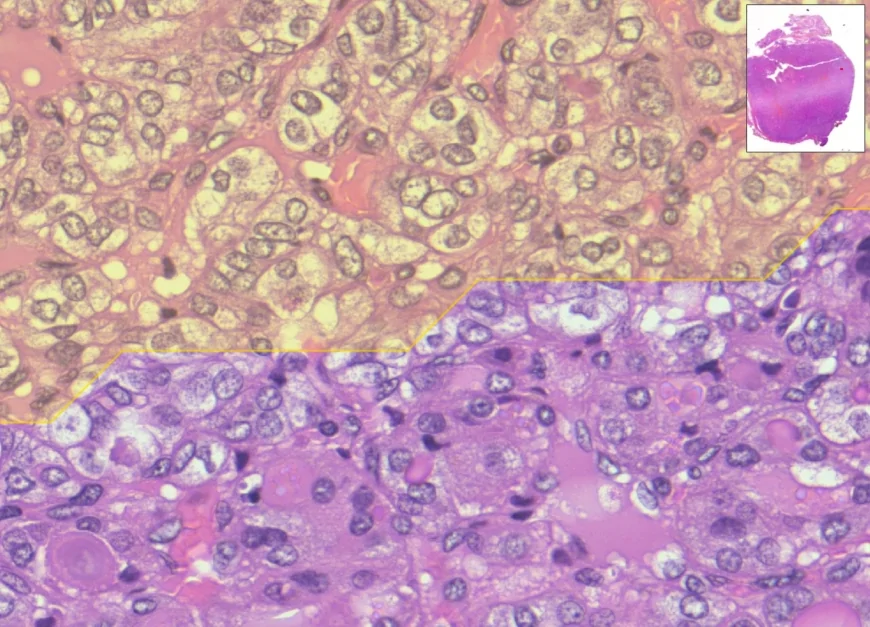

La patologia digitale: diagnosi ad alta risoluzione

Il contesto è la patologia digitale, ovvero l'analisi di vetrini istologici digitalizzati con scanner molto potenti in grado di produrre "fotografie" dei campioni, in cui è possibile zoomare fino al livello delle singole cellule. La prima difficoltà è che la diagnosi dipende da valutazioni su scale molto diverse, che insieme possono discriminare tumori da altre patologie non invasive o meno aggressive. Il sistema sviluppato nella ricerca mette in campo due reti neurali che lavorano in sequenza: un primo "occhio digitale" coglie i dettagli delle cellule; un secondo "occhio" considera la visione d'insieme dell'immagine. Mettendo insieme le due letture, MiThyCA indica dove conviene guardare prima.

Lo studio ha analizzato 73 immagini digitali di vetrini provenienti da più centri. Nei test il sistema ha indicato correttamente le aree di interesse in circa 8–9 casi su 10; per ogni vetrino ha impiegato pochi secondi. Le dimensioni dell'immagine non hanno influenzato in modo rilevante i tempi di calcolo.